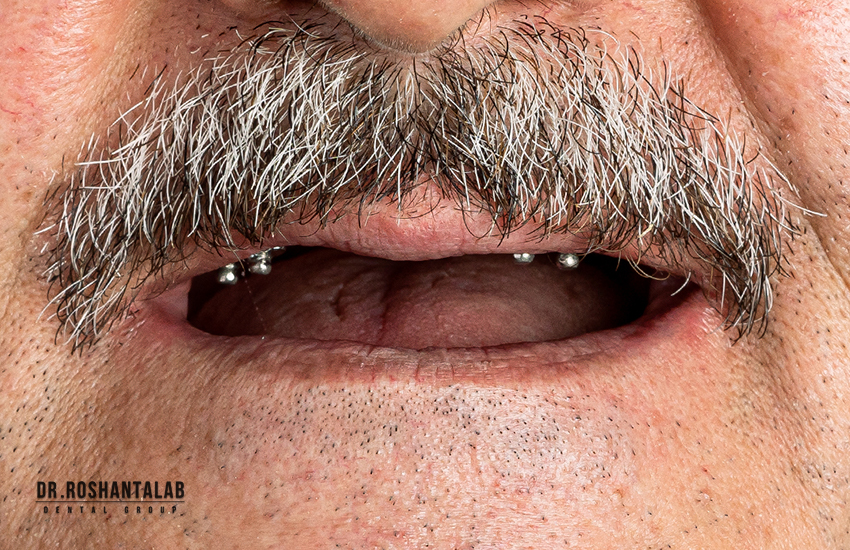

پروتز متکی بر ایمپلنت

پروتز متکی بر ایمپلنت میتواند شامل تمامی دندانها در فک بالا، تمامی دندانها در فک پایین و یا تمامی دندانها در فک بالا و پایین باشند به این صورت که دندان پزشک برای هر دندان از یک ایمپلنت استفاده نمیکند و این که تعداد کمتری از ایمپلنت استفاده میشود میتواند به دلایل مختلف مانند ارزان قیمتتر تمام شدن، گنجایش کم استخوان فک برای قرار گرفتن ایمپلنت به تعداد دندانها و… باشد.

معمولا در هر فک ۴ تا ۶ پایه ایمپلنت قرار میگیرید و پس از مشخص کردن جای دقیق ایمپلنتها پروتزهای دندانی بر آن اساس ساخته میشود و پس از ساخته شدن به ایمپلنت متصل میشوند.

ایمپلنت فول موس برای شخصی کلیه دندانهای خود را ازدستداده و تصمیم به بازسازی دندانهایش با ایمپلنت داشته باشد به کار می رود.